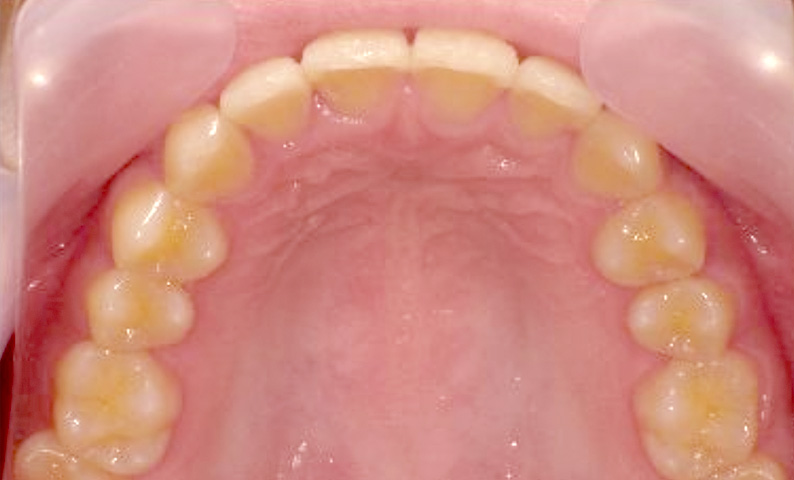

症例_020 上下顎の部分矯正

治療期間:6ヶ月金額:51万円+税女性前歯のガタガタ出っ歯

| Before | After |

|---|---|

|